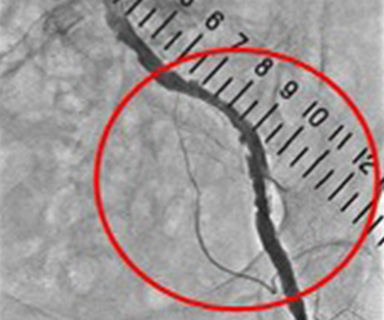

下肢動脈血管造影検査

この検査では閉塞性動脈硬化症の原因となる足へ流入する動脈が狭くなっているか、閉塞しているかを調べます。

閉塞性動脈硬化症になると足のへの血流量が減り、足の冷感・しびれ・痛みなどがあらわれ、ひどくなると潰瘍や壊死を起こすこともあります。また検査だけではなく狭くなった動脈を拡げる治療も行うことができます。

カテーテル操作をしやすい太い動脈(主に足の付け根)へ麻酔をし、そこからカテーテルを入れます。

狭くなった血管へカテーテルを進め、風船のついたカテーテルを膨らませ血管を拡げます。膨らませるだけでなくステントと呼ばれる金属のバネで固定し血管を拡げることもできます。

これを経皮的経管的血管形成術(PTA:percutaneous transluminal angioplasty)と呼びます。

膝付近の狭くなった動脈

(下肢動脈造影)